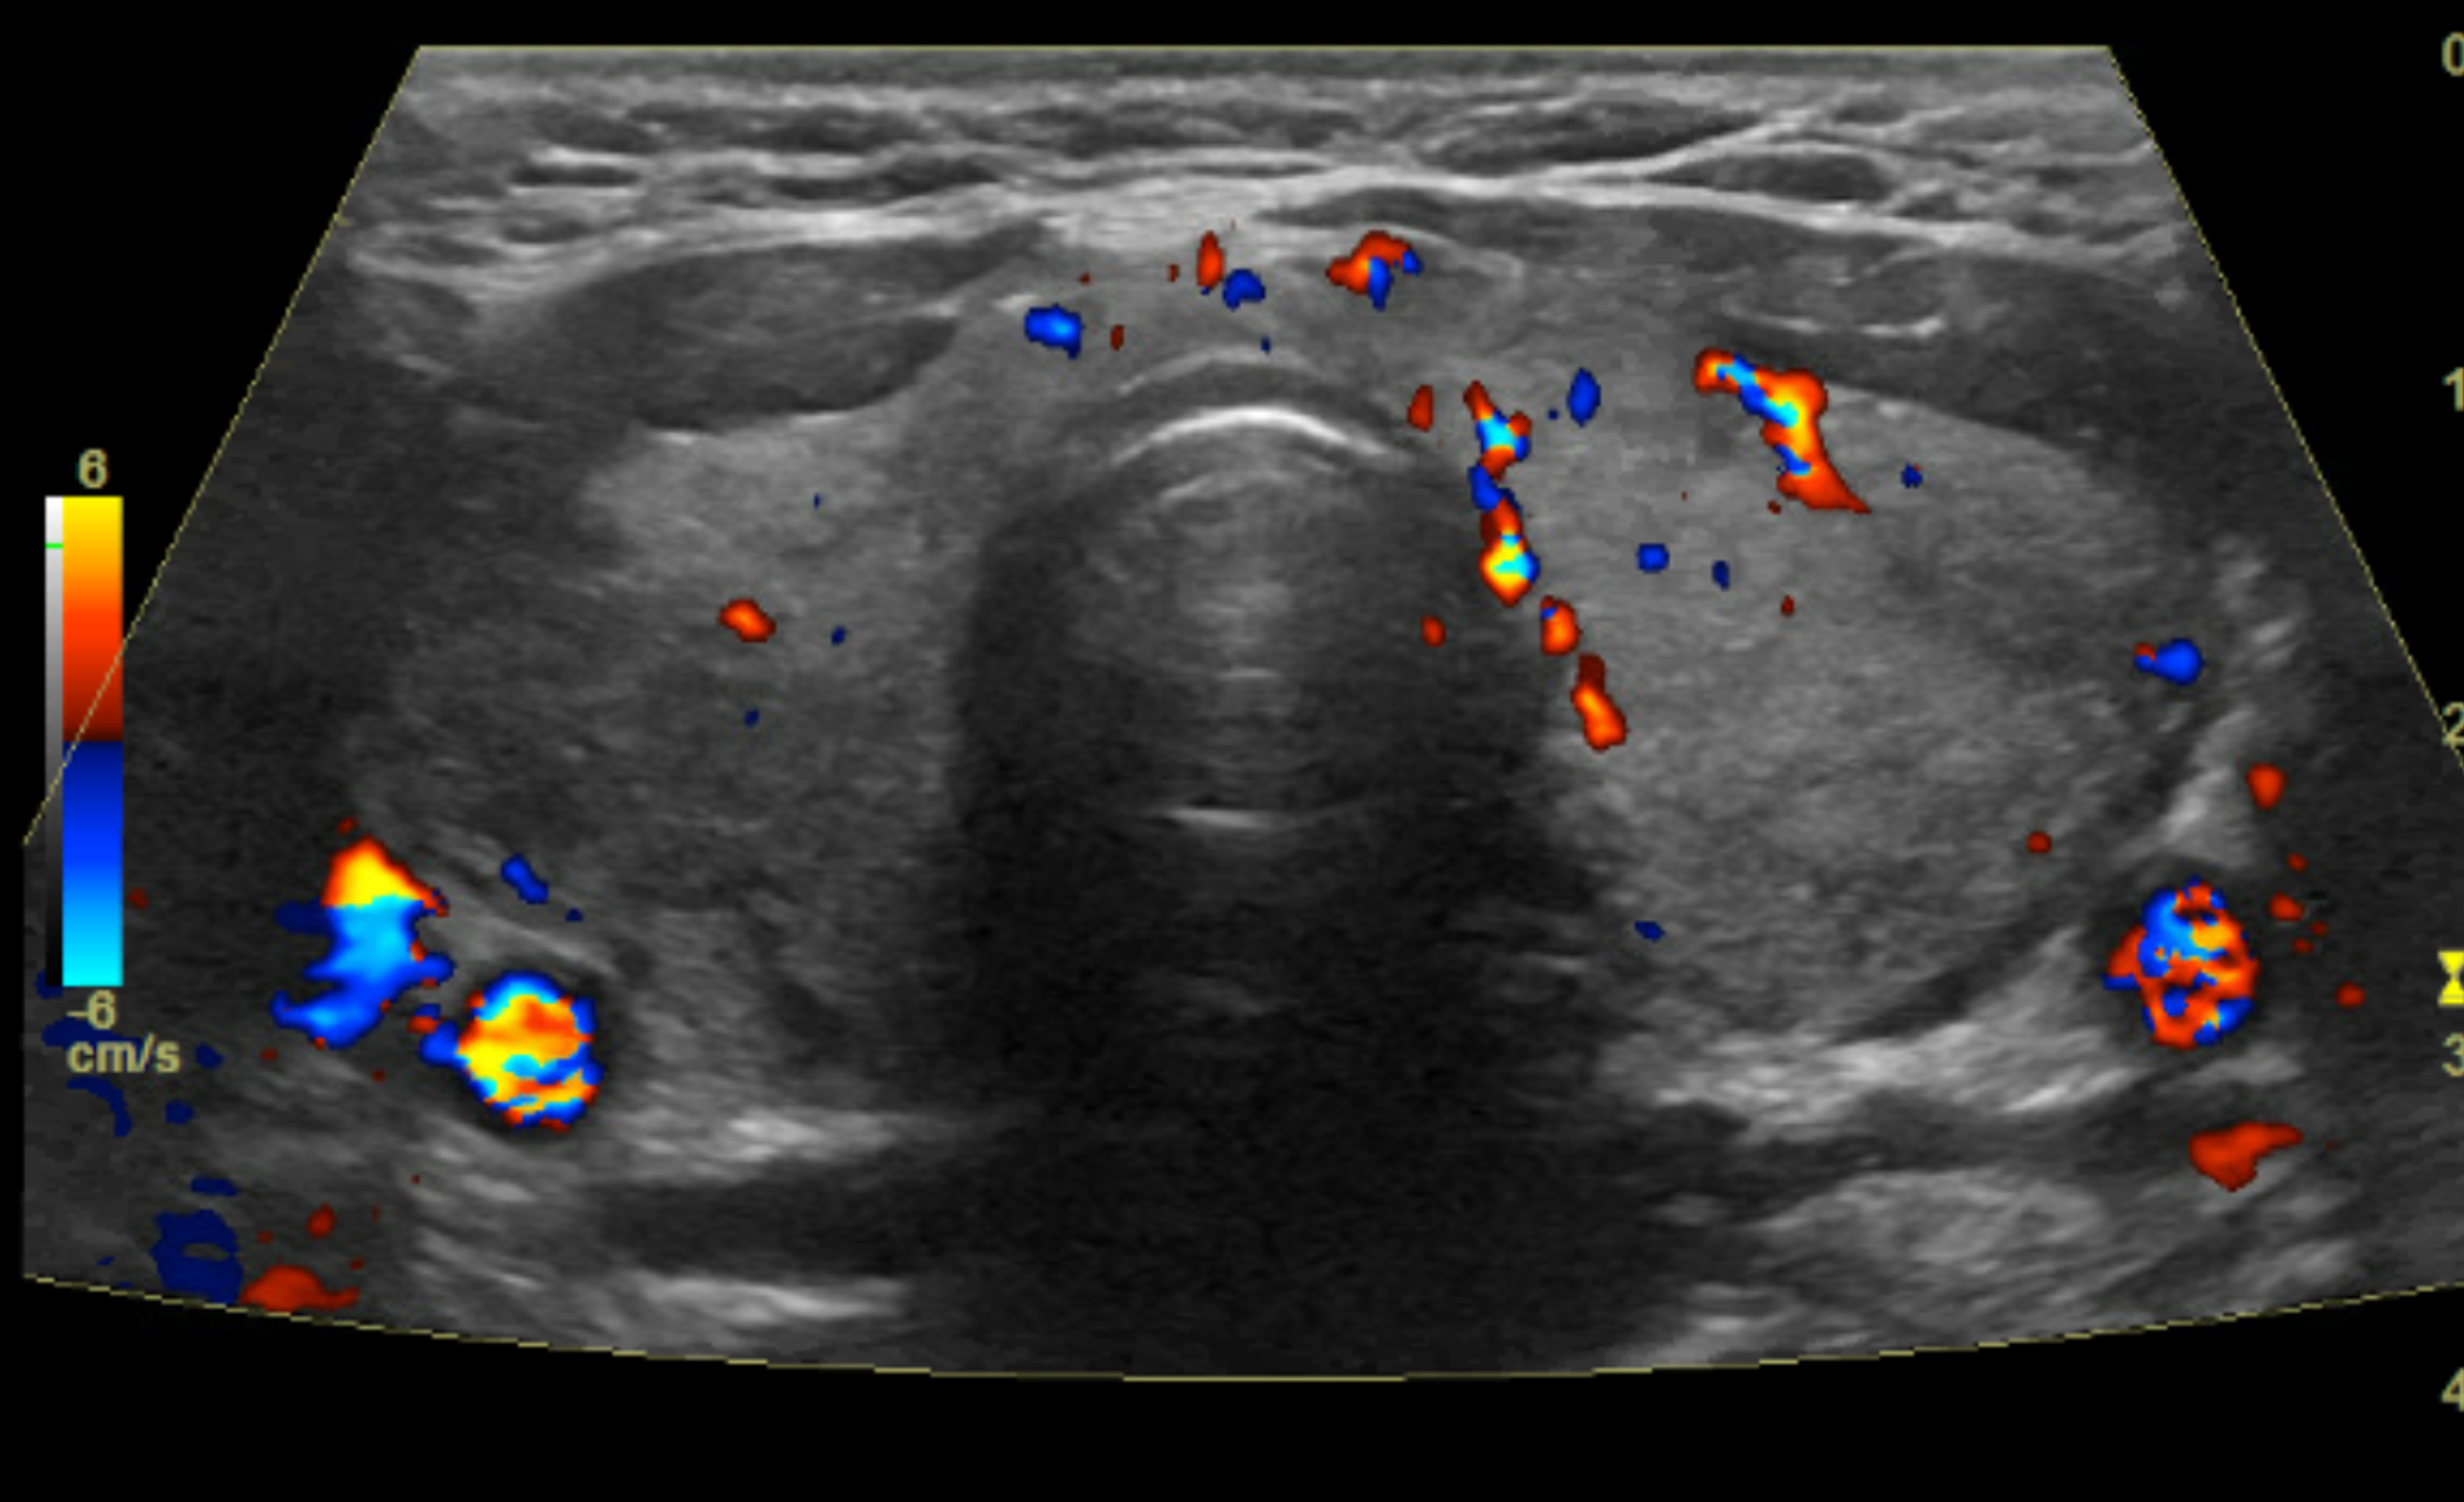

Graves Disease Ultrasound Images . graves’ disease is the most common cause of hyperthyroidism, followed by toxic multinodular goiter. graves’ disease is characterized by two sonographic features,. the diagnosis of graves’ disease is based on clinical and laboratory findings and ultrasound is usually not routinely required. Rarer causes include an autonomously functioning thyroid adenoma and thyroiditis. thyroid ultrasound takes a series of images of the thyroid gland and other neck structures and so the physician can assess them for. histopathological images of mild and severe follicular hyperplasia obtained from gd patients and correlation to laboratory and.

Graves Disease Thyroid Ultrasound Graves Disease Ultrasound Images graves’ disease is characterized by two sonographic features,. Rarer causes include an autonomously functioning thyroid adenoma and thyroiditis. thyroid ultrasound takes a series of images of the thyroid gland and other neck structures and so the physician can assess them for. graves’ disease is the most common cause of hyperthyroidism, followed by toxic multinodular goiter. histopathological. Graves Disease Ultrasound Images.